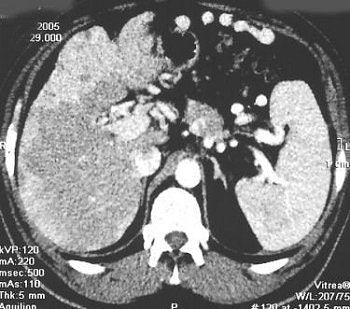

![]() |

Same patient. Above, CT scan 12 weeks after the start of the radionuclide treatment. Below, CT scan done six weeks after completed therapy of 90Y DOTA TATE. RECIST = disease stability. Serum CgA increased. Patient was clinically well at six-month follow-up. Images courtesy of Dr. Jaroslaw Cwikla.